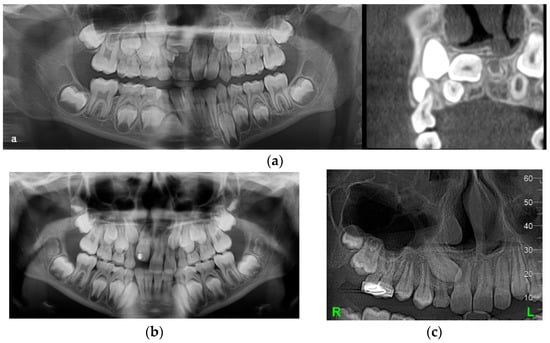

A 10-year-old boy sought orthodontic treatment for esthetic reasons due to the absence of the upper left central incisor, and malalignment of upper front teeth, and was without a history of trauma. The patient had permanent dentition with the persistence of the right deciduous canine and left lateral incisors, macrodontia and class 1 Angle malocclusion. A panoramic X-ray revealed the impaction of the left central incisor due to a supernumerary impacted tooth blocking the eruption path of the central incisor. A DC was associated with the impacted left upper incisor, and its root was not in the axis of the crown. The space for the upper left canine was closed because the lateral incisor was displaced in a distal position by the supernumerary tooth, the canine bulging buccally (Figure 3a).

(a) Impacted upper left central incisor blocked by a DC surrounding its crown and a supernumerary tooth. (b) Abnormal shape of the canine, root DL of the upper left central incisor, and a new tooth bud developing in the lower arch.

The objective of the orthodontic treatment was to preserve all the permanent teeth, as the replacement of any frontal teeth is very challenging despite the successful techniques in periodontology and implantology. The treatment started with surgery, including extraction of the supernumerary tooth and marsupialization of its DCs. A removable appliance was worn to maintain the space and eventually for orthodontic traction of the impacted teeth. The eruption process of the central incisor was monitored periodically by X-ray exams, and it was found that the central incisor erupted very slowly, with a tendency for impaction, and the decision was made to apply orthodontic traction to bring it into the oral cavity. At the same time, the canine changed its eruption path in a mesial direction, in transposition with the lateral incisor. The abnormal shape of the canine, with a big cingulum, like a supernumerary cusp, root DL of the central incisors and a new tooth bud between left mandibular premolars (Figure 3b), could be seen on the panoramic X-ray. In this clinical case, the root DL was seen only in the impacted central incisor associated with the DC, and the cause of DL could be the lack of space for the root to develop in a normal direction. This case is another case of dental anomaly pattern (DAP) or associated dental anomaly (ADA)—macrodontia, impaction, supernumerary teeth, DL and DC, transposition, an early eruption of permanent teeth, and DL might also have a genetic origin.

A 10-and-a-half-year-old girl was referred by her dentist after unexpectedly finding two big DCs associated with the mandibular premolars on an X-ray. The patient had a severe class II div 1 malocclusion, being a thumb-sucker, and an early mixed dentition due to a delayed eruption. All mandibular deciduous molars had fillings and root canal treatments that could advocate for DCs of inflammatory origin. The panoramic X-ray revealed on the right side a DC, associated with the second premolar, and on the left side both premolars are included in another DC, which was bilocular (Figure 4a). The first left premolar was in a horizontal position with the crown facing labially and root lingually (Figure 4b). The eruption of the left lateral incisor and canine was blocked by the lack of space, due to a supernumerary erupted mandibular incisor.

(a) Initial panoramic X-ray revealed large DCs on both sides of the mandible. (b) CBCT image showing the labiolingual orientation of the lower left first and second premolars. (c) CBCT showing root DL of the left first premolar.

An 8-year-old boy was brought by his parents for a second opinion. His parents’ concern was the absence of the upper right incisors. He would have been wearing a removable appliance for maxillary expansion, but he could not accept it. The patient had a class III Angle malocclusion and a delayed mixed dentition without central and lateral upper right incisors. The panoramic X-ray showed that the upper right central incisor was impacted in a very high position, almost horizontally, with the root in the palatal bone. There was also a congenitally missing lateral incisor and a supernumerary tooth, partially below the central incisor. The CBCT also revealed a DC-associated upper central incisor (Figure 6a).

(a) Impaction of the central incisor, congenitally missing lateral incisor, and a supernumerary tooth were noticed on the initial panoramic X-ray and CBCT. (b) Panoramic X-ray showing the root DL of all the incisors. (c) CBCT—upper right impacted canine presenting a DC.

Along with the supernumerary tooth extraction, the marsupialization of the DC was performed, and the central incisor started its eruption. After a while, a second surgical intervention was done to bond an attachment for orthodontic traction of the central incisor, which had an abnormal mesiodistal width—gigantism. Because of its size, the space for the missing right lateral incisor was closed, and there was not enough space for the canine, which remained impacted, included in a DC. The new panoramic X-ray showed the root DL of all the incisors, being more evident on the left side (Figure 6b). For the left central incisor, the root DL could be explained by the closed contact of DC-associated right central incisor DC with its root at different vertical levels, as seen on the CBCT. For establishing the treatment plan, the long-term prognosis of the right canine had to be taken into consideration with the aid of a new CBCT. It was noted on the CBCT that the canine is impacted, included in a bigger DC than initially seen, and with root DL (Figure 6c). The case described above was a DAP of genetic origin, impaction of the central incisor, congenitally missing lateral incisor associated with canine impaction, and DCs including impacted teeth. The root DL of the incisors and right canine could be caused in this case not only by DC and deep impaction of the central incisors, but also by genetic causes.